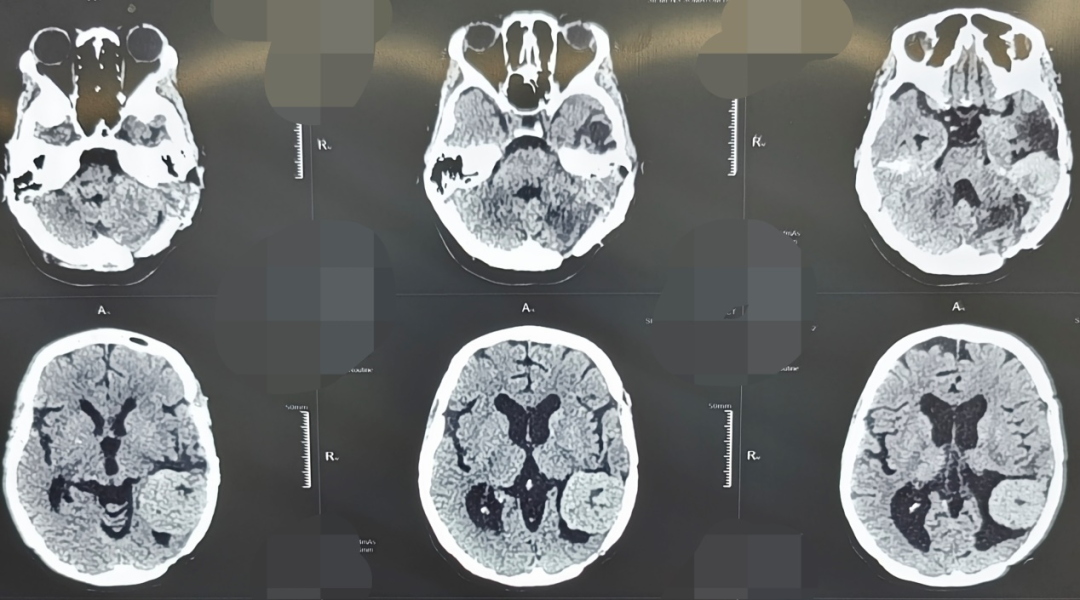

45岁的张女士,因“头晕、耳鸣伴听力下降”来到西安市红会医院就诊。她曾在2011年和2017年两次因颅内血管周细胞瘤于外院接受开颅手术治疗,并进行术后放化疗。此次入院后影像学检查显示,肿瘤在左侧颞部及桥小脑角区复发。该区域毗邻脑干、面神经、听神经及多条重要血管,素有“生命禁区”之称,手术风险极高。

更为严峻的是,进一步检查发现患者体内存在高度疑似肝脏转移灶,提示疾病可能已进入晚期;同时合并严重贫血、心脏电生理异常等多种并发症。病情复杂、风险叠加,任何环节处置不当均可能导致严重后果。